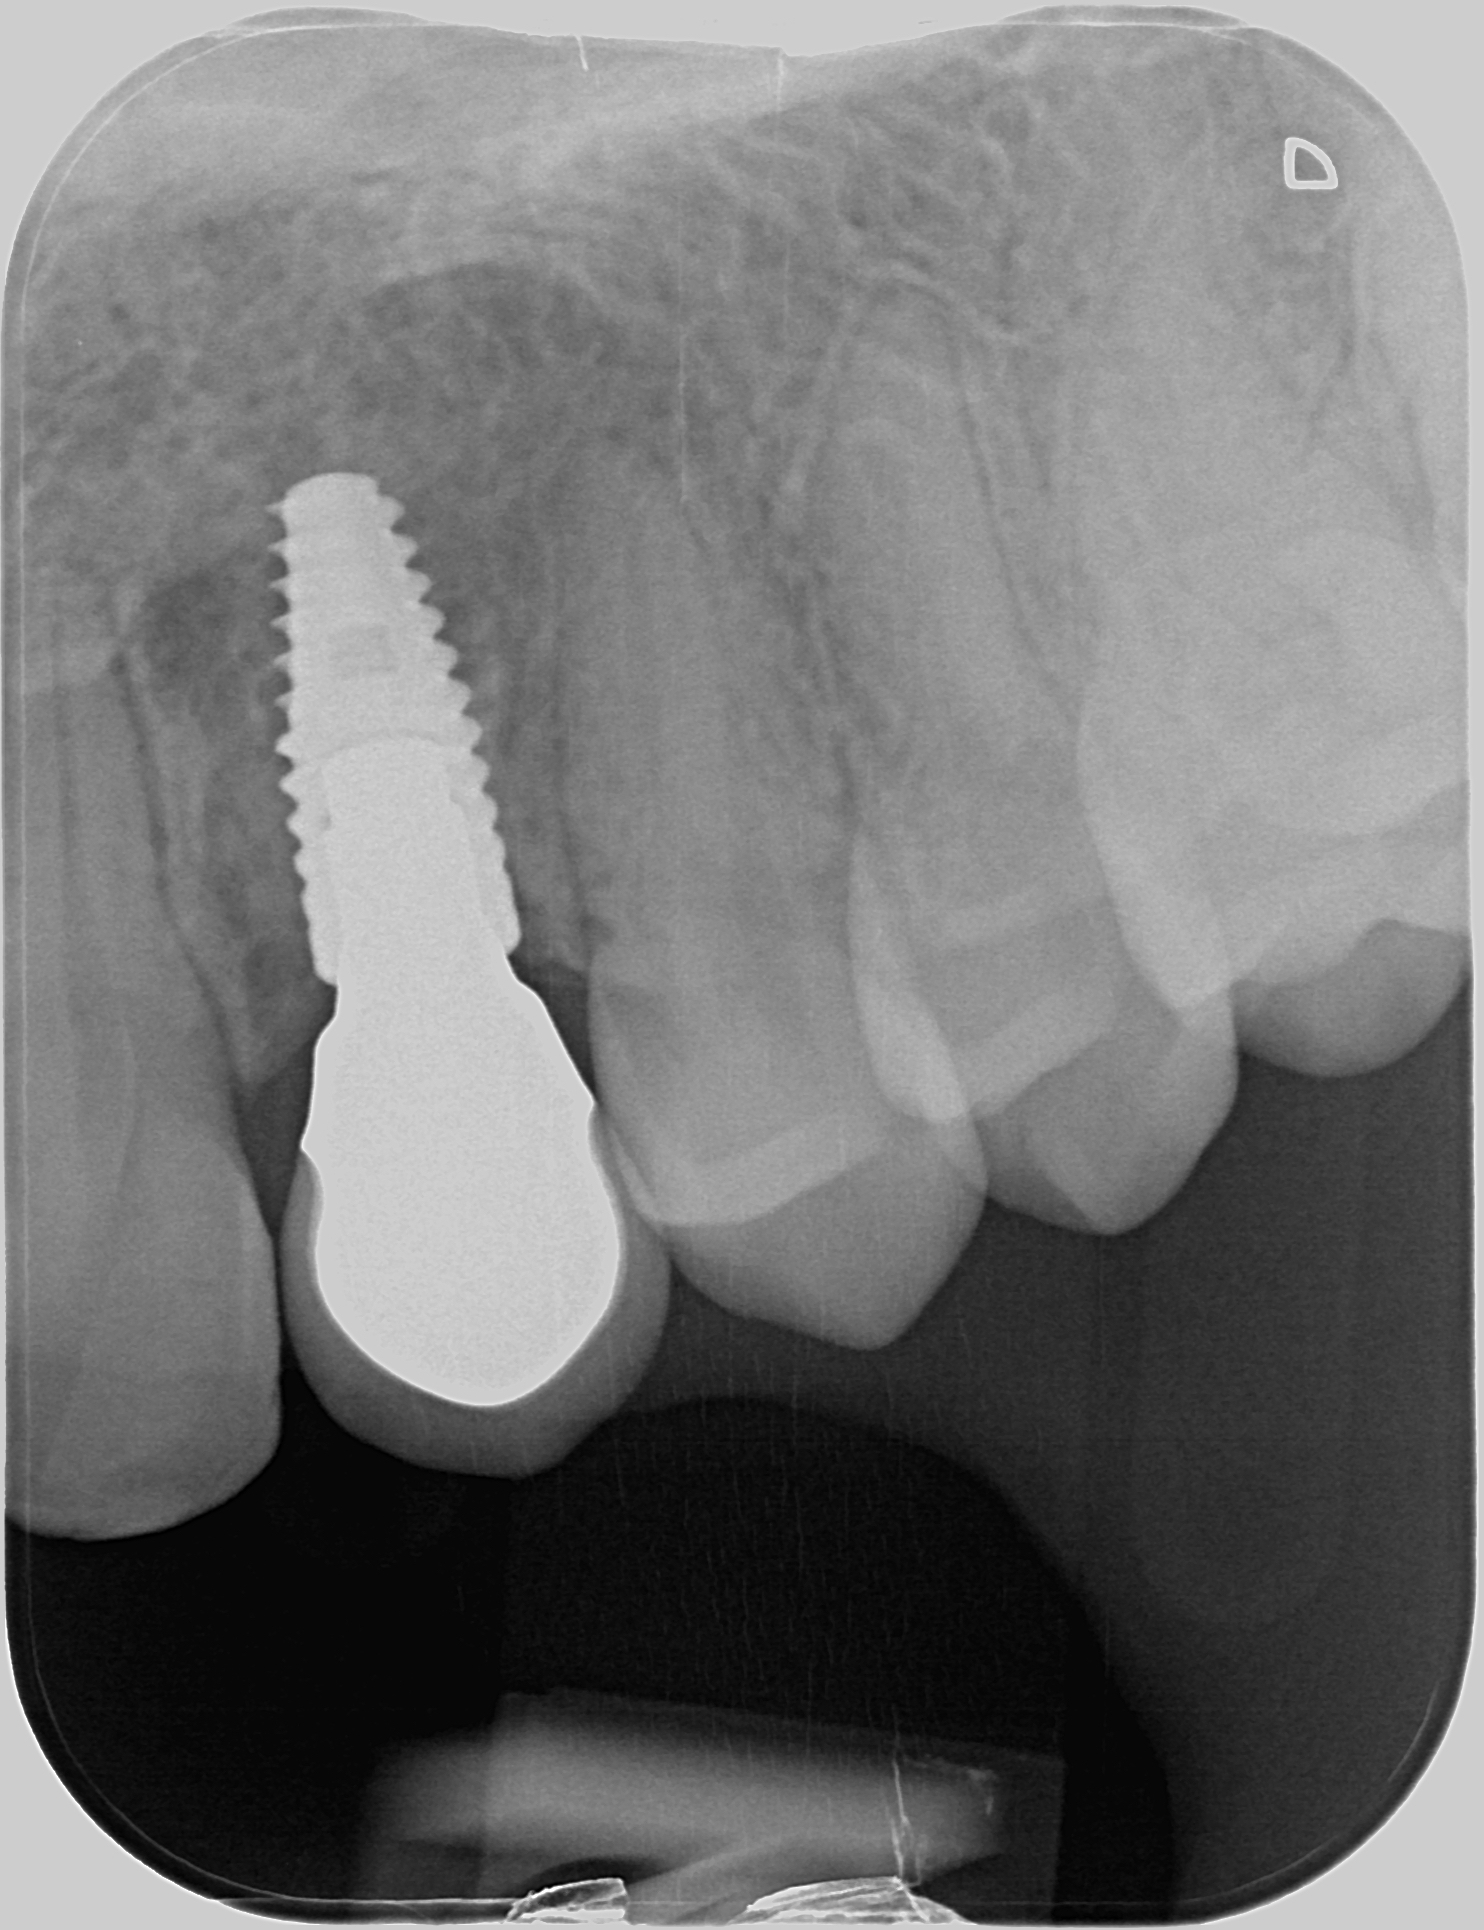

Synnynnäisesti puuttuva kulmahammas. Alkukuvissa hammas on korvattu muovisella kevytsillalla. Silta purettu pois ja asetettu implantti puuttuvan hampaan tilalle. Kirurgina Jarno Savolainen eSmile Helsinki. Hammasteknikkomestari Aki Lindén.

Implantti asetettu paikoilleen. Kevytsilta kiinnitetty takaisin paikoilleen väliaikaiseksi ratkaisuksi.

Alkutilanne ennen kevytsiltaa. Kulmahammas poikittain syvällä luun sisällä, maitohammas pysyvän kulmahampaan paikalla. Hoidon aikana molemmat poistettu. Ja implantti asetettu paikoilleen